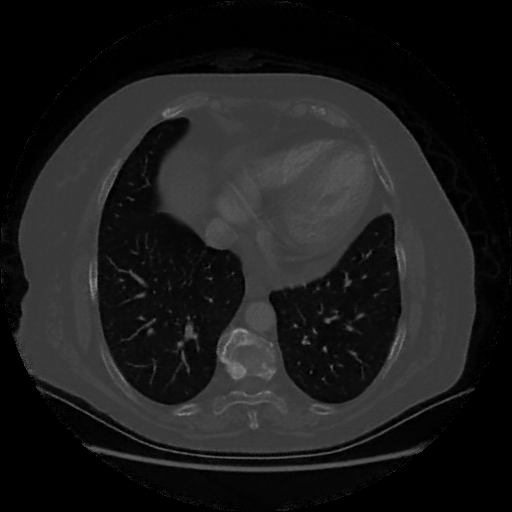

Reconstructed NATIVE CT scan (cycle consistency)

No window - Raw intensity values

Lung window (WL -600, WW 1500 β†’ Low βˆ’1350, High +150)